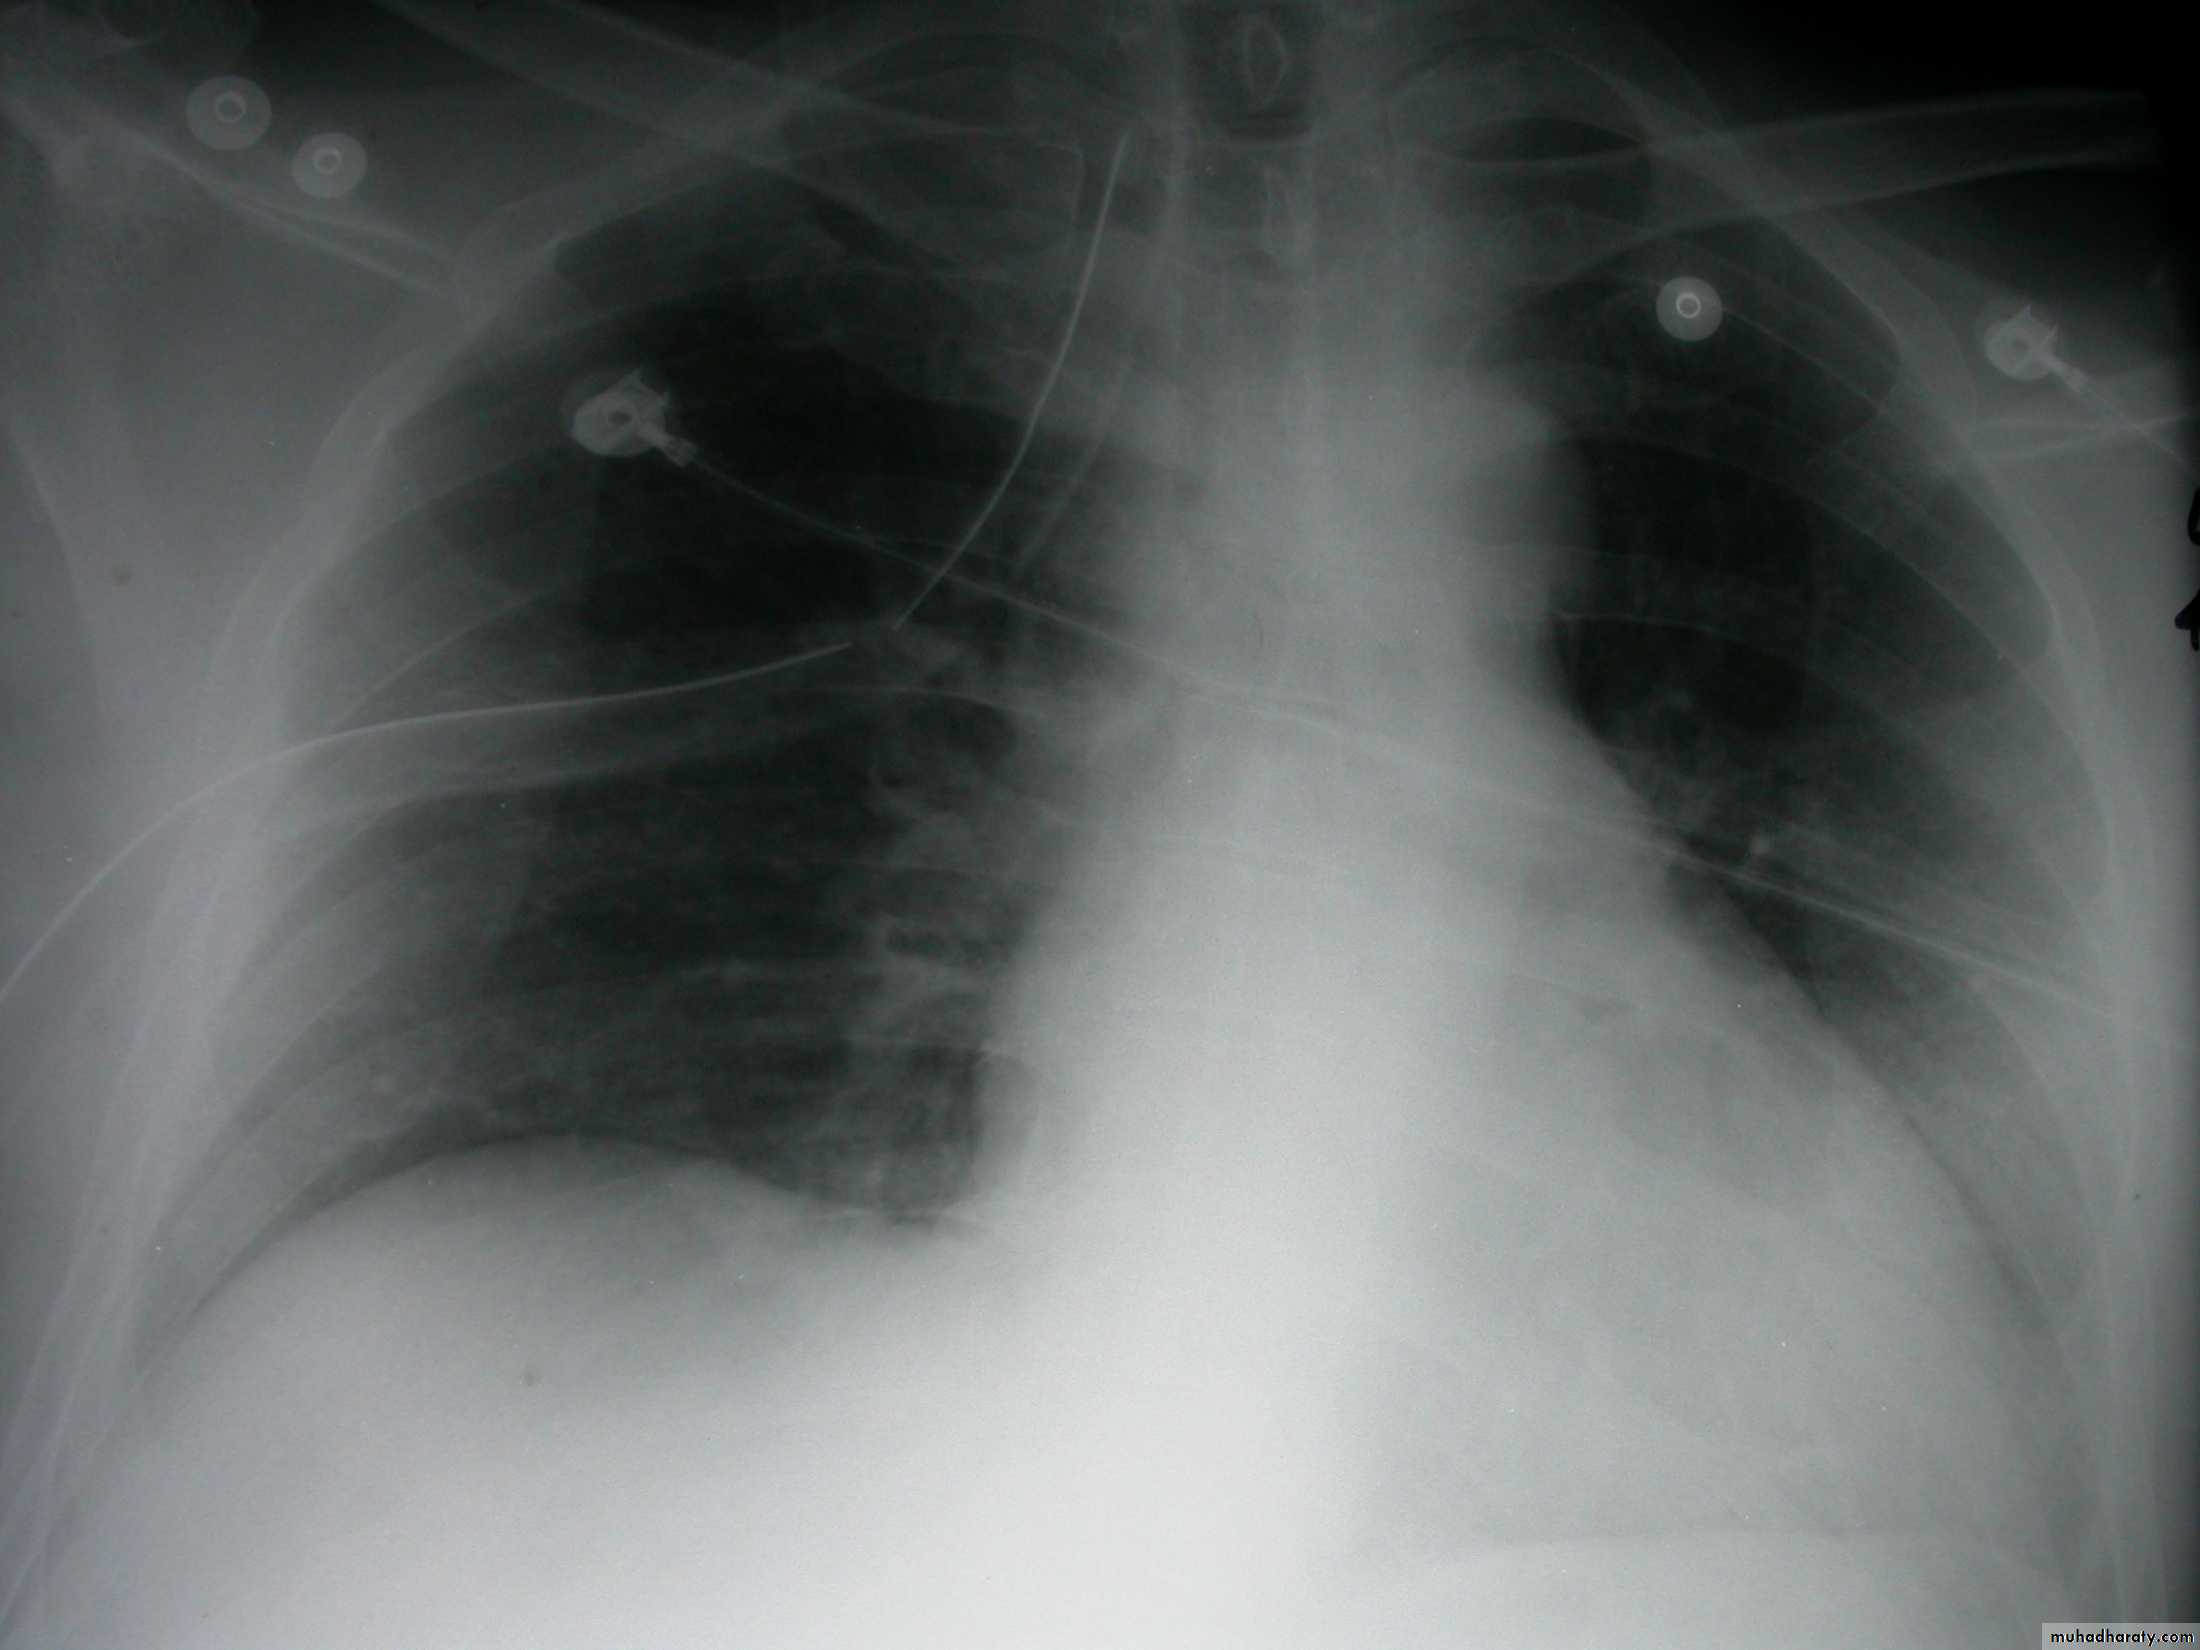

Severe dyspnea with shock

Tension PneumothoraxTension Pneumothorax

(Collapse) (Massive plural effusion)